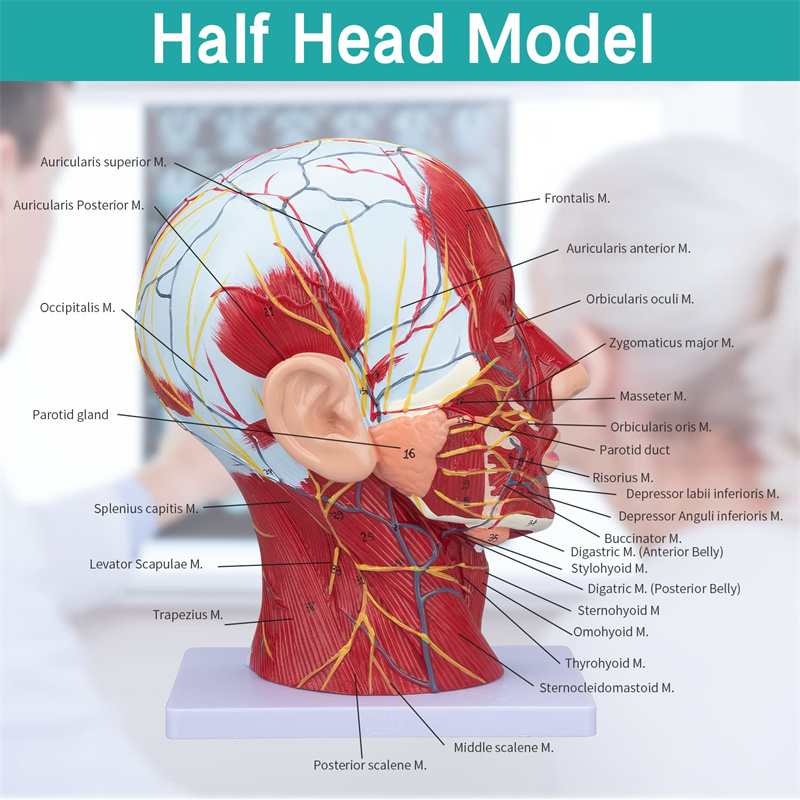

【ਉੱਚ ਕੁਆਲਟੀ】 ਦਿਮਾਗ ਦੇ ਸਰੀਰ ਵਿਗਿਆਨਕ ਮਾਡਲ, ਗੈਰ-ਜ਼ਹਿਰੀਲੇ ਵਾਤਾਵਰਣ ਦੇ ਅਨੁਕੂਲ ਪੀਵੀਸੀ ਸਮੱਗਰੀ ਦਾ ਬਣਿਆ, ਸਾਫ ਕਰਨਾ ਅਸਾਨ ਹੈ. ਸਰੀਰ-ਚਿੱਤਰ ਨੂੰ ਹੱਥ ਨਾਲ ਪੇਂਟ ਕੀਤਾ ਜਾਂਦਾ ਹੈ ਅਤੇ ਵੇਰਵੇ ਵੱਲ ਪੂਰਾ ਧਿਆਨ ਨਾਲ ਇਕੱਠਾ ਕੀਤਾ ਜਾਂਦਾ ਹੈ.

【ਸਤਹੀ ਨਿ ur ਰੋਵਸਕੂਲਰ ਮਾਸਪੇਸ਼ੀ ਦਾ ਮਾਡਲ】 ਉੱਚਿਤ ਵਿਸਥਾਰਪੂਰਕ, ਨੰਬਰ ਮਾਰਕ ਕੀਤੇ, ਕੰਬਦੇ ਕੰ the ੇ, ਨਾੜੀ ਅਤੇ ਗਰਦਨ ਦੇ ਅੰਦਰੂਨੀ structures ਾਂਚਿਆਂ ਦੀ ਸਮਝ ਨੂੰ ਡੂੰਘਾ ਕਰੋ. ਲਾਲ-ਧਮਣੀ, ਨੀਲੀ-ਨਾੜੀ, ਪੀਲੇ-ਨਸ.

【ਵਿਸ਼ੇਸ਼ਤਾਵਾਂ】 ਦਾ ਸਾਹਮਣਾ ਕੀਤੇ ਚਿਹਰੇ ਦੀਆਂ ਸਤਹੀ ਮਾਸਪੇਸ਼ੀਆਂ ਨੂੰ ਦਰਸਾਉਂਦਾ ਹੈ; ਸਤਹੀ ਖੂਨ ਦੀਆਂ ਨਾੜੀਆਂ ਅਤੇ ਚਿਹਰੇ ਦੀਆਂ ਨਾੜੀਆਂ ਅਤੇ ਖੋਪੜੀ; ਪੈਟੀਡ ਗਲੈਂਡ ਅਤੇ ਵੱਡੇ ਸਾਹ ਦੀ ਨਾਲੀ ਦੇ ਅੰਦਰੂਨੀ structures ਾਂਚਿਆਂ; ਸਰਵਾਈਕਲ ਰੀੜ੍ਹ ਦੀ ਸੋਗਿਤਲ ਕਰਾਸ-ਸੈਕਸ਼ਨ structure ਾਂਚਾ.

ਇਹ ਮਾਡਲ ਮਨੁੱਖ ਦੇ ਸੱਜੇ ਸਿਰ ਅਤੇ ਮਨੁੱਖ ਦੇ ਮੱਧ ਸੇਂਟਟਲ ਭਾਗ ਦਾ ਵੇਰਵਾ ਦਰਸਾਉਂਦਾ ਹੈ. ਸਤਹੀ ਵੀ ਸ਼ਾਮਲ ਹੈ

ਖੁੱਲੇ ਚਿਹਰੇ ਦੇ ਮਾਸਪੇਸ਼ੀ; ਸਤਹੀ ਖੂਨ ਦੀਆਂ ਨਾੜੀਆਂ ਅਤੇ ਚਿਹਰੇ ਅਤੇ ਖੋਪੜੀ ਦੀਆਂ ਨਾੜੀਆਂ; ਅੰਦਰੂਨੀ structures ਾਂਚਿਆਂ

ਪੈਟੀਡ ਗਲੈਂਡ ਅਤੇ ਉਪਰਲੇ ਸਾਹ ਦੀ ਨਾਲੀ; ਸਰਵਾਈਕਲ ਰੀੜ੍ਹ ਦੀ ਸੋਗਿਤਲ ਕਰਾਸ-ਸੈਕਸ਼ਨ structure ਾਂਚਾ.

ਮਾਡਲ ਨੇ ਸਿਰ ਅਤੇ ਗਰਦਨ ਅਤੇ ਗਰਦਨ ਦੇ ਮੱਧਮ ਅਤੇ ਪਾਰਦਰਸ਼ੀ ਸਮੂਹਾਂ ਅਤੇ ਇਸ ਦੇ ਨਾੜੀ ਅਤੇ ਨਸਾਂ ਦੇ structures ਾਂਚਿਆਂ ਅਤੇ ਨਸਾਂ ਦੇ structures ਾਂਚਿਆਂ ਦਾ ਸਥਾਨਕ ਰੂਪ ਵਿਗਿਆਨ ਅਤੇ ਇਸ ਦੇ ਨਾੜੀ ਅਤੇ ਨਸਾਂ ਦੇ structures ਾਂਚਿਆਂ ਦਾ) ਕੁੱਲ 100 ਸਾਈਟ ਸੂਚਕਾਂ ਦੇ ਨਾਲ ਦਿਖਾਇਆ ਗਿਆ ਹੈ.

ਇਹ ਮਾਡਲ ਇੱਕ ਕੁਦਰਤੀ ਵੱਡਾ ਸਿਰ ਅਤੇ ਗਰਦਨ ਸਤਹੀ ਨਿ ur ਰੋਵਸਕੁਲਰ ਮਾਸਪੇਸ਼ੀ ਮਾਡਲ, 1 ਕੰਪੋਨੈਂਟ, ਚਿਹਰੇ ਅਤੇ ਖੋਪੜੀਆਂ ਦੇ ਸਤਹੀ ਮਾਸਪੇਸ਼ੀਆਂ ਦੇ ਵੇਰਵੇ ਦਿਖਾਉਂਦੇ ਹੋਏ, ਨਸਾਂ ਅਤੇ ਪੈਰੋਟਿਡ ਗਲੈਂਡ ਅਤੇ ਵੱਡੇ ਸਾਹ ਦੀ ਨਾਲੀ ਦਾ ਮੈਡੀਅਲ ਬਣਤਰ, ਅਤੇ ਸਰਵਾਈਕਲ ਰੀੜ੍ਹ ਦੀ ਸੋਗਟਲ ਸੈਕਸ਼ਨ ਦਾ structure ਾਂਚਾ